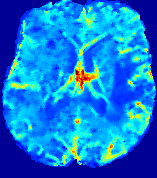

LesionRefer to captionRefer to captionRefer to captionRefer to captionRefer to captionRefer to caption𝐕rgbsubscript𝐕𝑟𝑔𝑏{\bf{V}}_{rgb}Refer to captionRefer to captionRefer to captionRefer to captionRefer to captionRefer to caption𝐕2subscriptnorm𝐕2{\|\bf{V}}\|_{2}Refer to captionRefer to captionRefer to captionRefer to captionRefer to captionRefer to captionRefer to caption3.53.53.52.82.82.82.12.12.11.41.41.40.70.70.70.00.00.0(mm/s)𝑚𝑚𝑠(mm/s)D𝐷DRefer to captionRefer to captionRefer to captionRefer to captionRefer to captionRefer to captionRefer to caption0.0200.0200.0200.0160.0160.0160.0120.0120.0120.0080.0080.0080.0040.0040.0040.0000.0000.000(mm2/s)𝑚superscript𝑚2𝑠(mm^{2}/s)Slice #1Slice #2Slice #3Slice #4Slice #5Slice #6

Figure 4: PIANO feature maps for another patient in the ISLES 2017 training set, where the lesion is located in the right hemisphere. Top row: segmented stroke lesion region (white) on different slices. The corresponding slices for the PIANO feature maps are shown in the following rows.

For a better insight into an estimated velocity field 𝐕𝐕{\bf{V}} and diffusion field 𝐃𝐃{\bf{D}}, we compute the following maps: (1) 𝐕rgbsubscript𝐕𝑟𝑔𝑏{\bf{V}}_{rgb}: Color-coded orientation map of 𝐕=(Vx,Vy,Vz)T𝐕superscriptsuperscript𝑉𝑥superscript𝑉𝑦superscript𝑉𝑧𝑇{\bf{V}}=(V^{x},V^{y},V^{z})^{T}, obtained by normalizing 𝐕𝐕{\bf{V}} to unit length and mapping its 3 components to red, green, blue respectively; (2) 𝐕2subscriptnorm𝐕2\|{\bf{V}}\|_{2}: 222 norm of 𝐕𝐕{\bf{V}}; (3) D𝐷D: scalar field in Eq. 5.

Fig. 3 and Fig. 4 show the PIANO feature maps estimated from two ISLES 2017 patients: all are highly consistent with the lesion in both cases. Details of the blood flow trajectories are revealed in 𝐕rgbsubscript𝐕𝑟𝑔𝑏{\bf{V}}_{rgb} by the ridged patterns and the sharp changes of colors in the unaffected (right) hemisphere, while the flat patterns appearing within the lesion provide little directional information about the velocity and indicate low velocity magnitudes. Velocity magnitudes are more directly visualized via 𝐕2subscriptnorm𝐕2\|{\bf{V}}\|_{2}, from which one can easily locate the lesion where 𝐕2subscriptnorm𝐕2\|{\bf{V}}\|_{2} is low. D𝐷D also indicates lower diffusion values in the lesion, though with less contrast potentially due to the fact that it captures the accumulated effect of CA diffusion at the voxel-level.